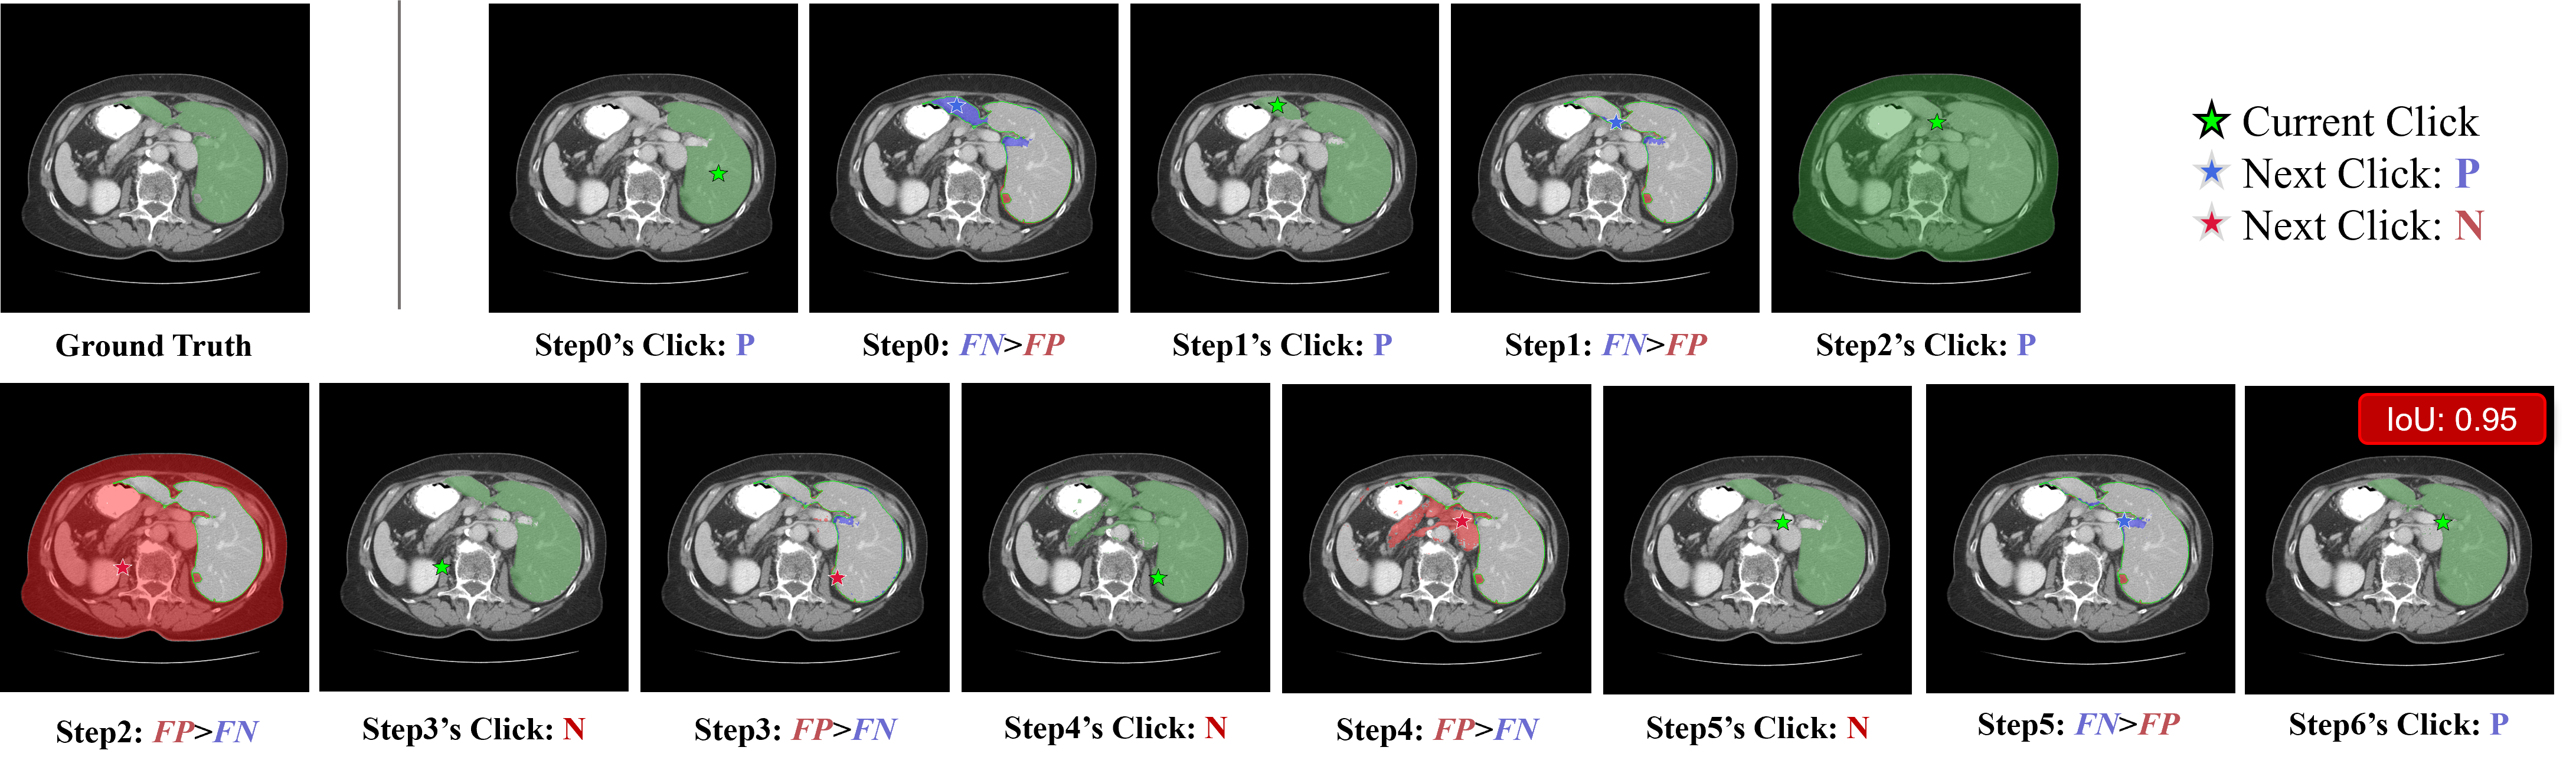

where Mlogits(0)M_{logits}^{(0)} is initialized as None. This iterative process continues until the IoU exceeds a threshold τiou\tau_{iou} or the maximum step count TmaxT_{max} is reached. The implementation logic is detailed in Algorithm 1. An example process is depicted as Fig. 5.

Figure 5: An illustrative example of the automated trajectory generation process for liver segmentation. The algorithm progressively refines the predicted mask through iterative interactions.

For each iteration (e.g., Step 0), two visualization panels are presented: (1) The

first image displays the current segmentation state, showing the predicted mask (green translucent overlay) generated by the current click (marked by a green star). (2) The second image illustrates the error analysis against the Ground Truth (delineated by a green outline). The differences are visualized as blue translucent regions for False Negatives (FN, under-segmentation) and red translucent regions for False Positives (FP, over-segmentation). The star in this panel indicates the calculated next action based on the largest error region: a blue star denotes a Positive Click (P) to correct under-segmentation, while a red star denotes a Negative Click (N) to correct over-segmentation.